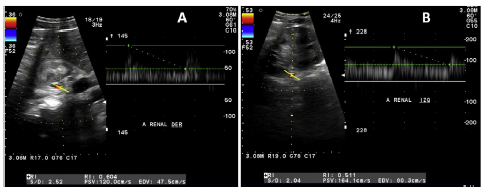

Given the suspicion of renovascular hypertension, aDoppler was practiced with the following findings (Fig. 2): maximum systolic velocity of 120 cm/s in the right renal arteryat the ostium and 120 cm/s at the hilum, with a resistanceindex of 0.60. The left renal artery evidenced a maximumsystolic velocity of 137 cm/s at the ostium and 164 cm/s atthe hilum, with a resistance index of 0.51. These normalvalues do not support the diagnosis of renovascular hypertension; therefore, to completely rule out this possibility, a99mTc-DMSA renal scintigram with captopril was performed, documenting baseline glomerular filtration rate in the leftkidney of 149.3 ml/min and the right kidney of 79.9 ml/min; postcaptopril: 232.6 ml/min and 156.4 ml/min, respectively. At follow-up, exclusive renal disease activity was foundwith normalization of acutephase reactants, yet a progressive drop in glomerular filtration rate. At the fourthyear of follow-up, creatinine increased up to 3.45 mg/dlwith a glomerular filtration rate of 34 ml/min and persis-tence of hematuria and albuminuria of 1840 mg in 24 h. Anephritic syndrome was diagnosed, and the following studies were conducted: anti-neutrophil cytoplasm antibodies,complement profile, systemic lupus erythematosus, and viralpanel, reported as normal. A renal biopsy was accomplished,demonstrating focal and segmental glomerulosclerosis with acollapsing variety (Fig. 3). High-dose glucocorticoid treatmentwas initiated (prednisone 50 mg/day-1 mg/kg/day-), switching methotrexate to azathioprine at 2 mg/kg/day, with noresponse: nitrogen compounds were elevated, with a serumcreatinine of 8.32 mg/dl. Renal replacement therapy was started with hemodialysis. The patient is under follow-up withno data on extrarenal vasculitis activity.

Figure 2 Doppler ultrasound of renal arteries. A) Right: maximum systolic velocity of 120 cm/s at the ostium level and 120cm/s at the hilum, with a resistance index of 0.60. B) Left: maximum systolic velocity of 137 cm/s at the ostium and 164 cm/s at the hilum, with a resistance index of 0.51.